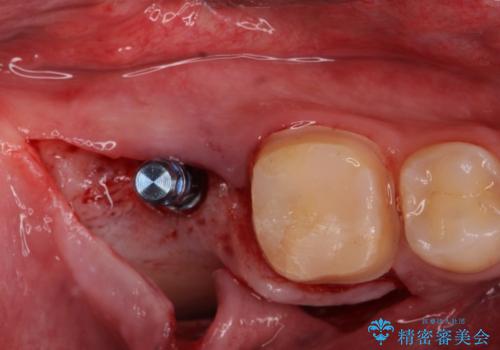

抜歯したところは抜歯後骨の治癒を待ち、CTを撮影しインプラント治療ができる事(骨の厚みなど)確認し治療を行いました。

右下の被せ物を外し虫歯を除去したところ虫歯が深く保存が難しい状態だったので抜歯を行いました。